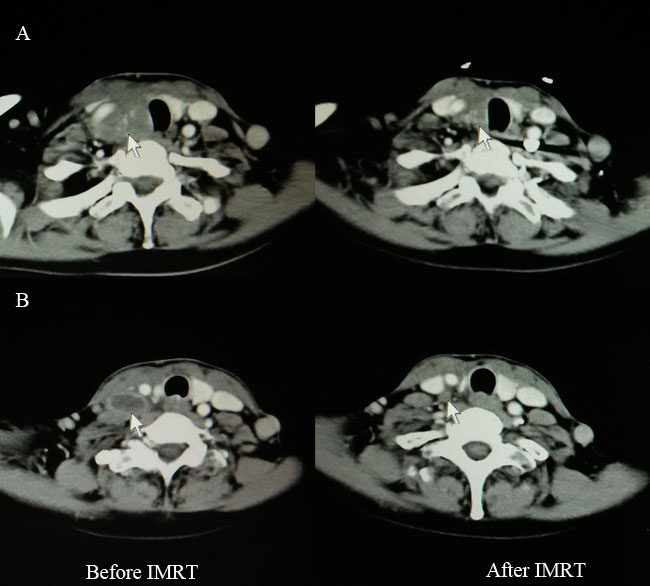

Figure 1: Computed tomography findings before (left) and after (right) IMRT for one patient with CASTLE who received palliative resection. A. Disease extent for primary tumor (white arrow). B. Disease extent for involved lymph node (white arrow). IMRT, intensity-modulated radiotherapy; CASTLE, carcinoma showing thymus-like differentiation.

Two patients received palliative resection because of tumor invasion to the adjacent great vessels. IMRT was administered at a radical dose of 66 Gy in 33 fractions to them. One cycle of chemotherapy (paclitaxel 135mg/m2, day 1, cisplatin 25mg/m2/d, days1-3) was given to one of the patients concurrently with IMRT. Complete regression (CR) of the lymph node and partial regression (PR) of the primary tumor was obtained after IMRT (Figure 1). Both patients were alive with stable disease (SD) at the time of last follow-up. Tsutsui et al [5] reported a similar case in 2013. After radiotherapy, CR of the tumor was achieved and CT findings did not show local recurrence for about 7 years. In the study by Chow et al [16], radiotherapy combined with chemotherapy rendered the inoperable disease operable for one patient with locally advanced disease. These therefore remind us that curative IMRT combined with or without chemotherapy seems to be an alternative for patients with unresectable disease.